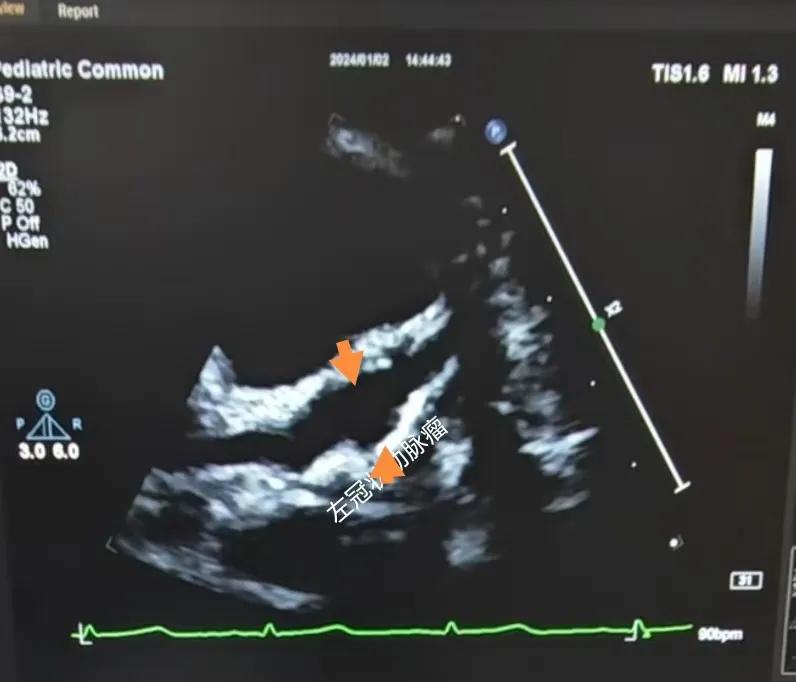

(川崎病患兒:左冠狀動脈瘤)

川崎病是兒童時期一種急性全身非特異性血管炎,對心臟的損害主要是冠狀動脈,可導(dǎo)致冠狀動脈的擴張、冠狀動脈瘤及冠狀動脈血栓,這些損傷可能會引起心肌梗死,目前川崎病已經(jīng)成為兒童獲得性心臟病的主要原因。心臟超聲診斷川崎病,特別是在臨床癥狀不典型或?qū)嶒炇覚z查結(jié)果不明確的情況下。通過心臟超聲,可以觀察到冠狀動脈的擴張情況,這是診斷川崎病的一個關(guān)鍵指標(biāo)。心臟超聲能夠精確測量冠狀動脈的內(nèi)徑及擴張程度,對于診斷冠狀動脈瘤形成具有特異性。這對于早期診斷和及時治療至關(guān)重要。還可以檢測到心臟其他一些并發(fā)癥,如心肌病、心包炎和心律失常等。可以評估心臟的整體功能和心肌運動狀態(tài),這有助于判斷疾病的嚴重程度和治療效果。在疾病的恢復(fù)期,可以用于監(jiān)測冠狀動脈的恢復(fù)情況,并及時發(fā)現(xiàn)可能的復(fù)發(fā)或新的并發(fā)癥。

川崎病的超聲診斷標(biāo)準:

冠脈內(nèi)徑超過正常值或某一節(jié)段內(nèi)徑超過相鄰節(jié)段內(nèi)徑的1.5倍時,即可診斷冠脈擴張,其正常值參考標(biāo)準: <3歲,冠狀動脈內(nèi)徑<2.5mm; 3~9歲,冠脈內(nèi)徑<3.0mm; >9歲,冠狀動脈內(nèi)徑<3.5mm。

采用左右冠狀動脈的直徑與主動脈直徑之比來判斷冠狀動脈擴張與冠狀動脈瘤:

A.冠狀動脈擴張 :冠狀動脈內(nèi)徑≤4mm. 其與主動脈根部內(nèi)徑之比0.16~0.3 。

B.冠狀動脈瘤:冠狀動脈內(nèi)徑>4mm,其與主動脈根部內(nèi)徑之比>0.3。

C.巨大冠脈瘤冠狀動脈內(nèi)徑>8mm 。